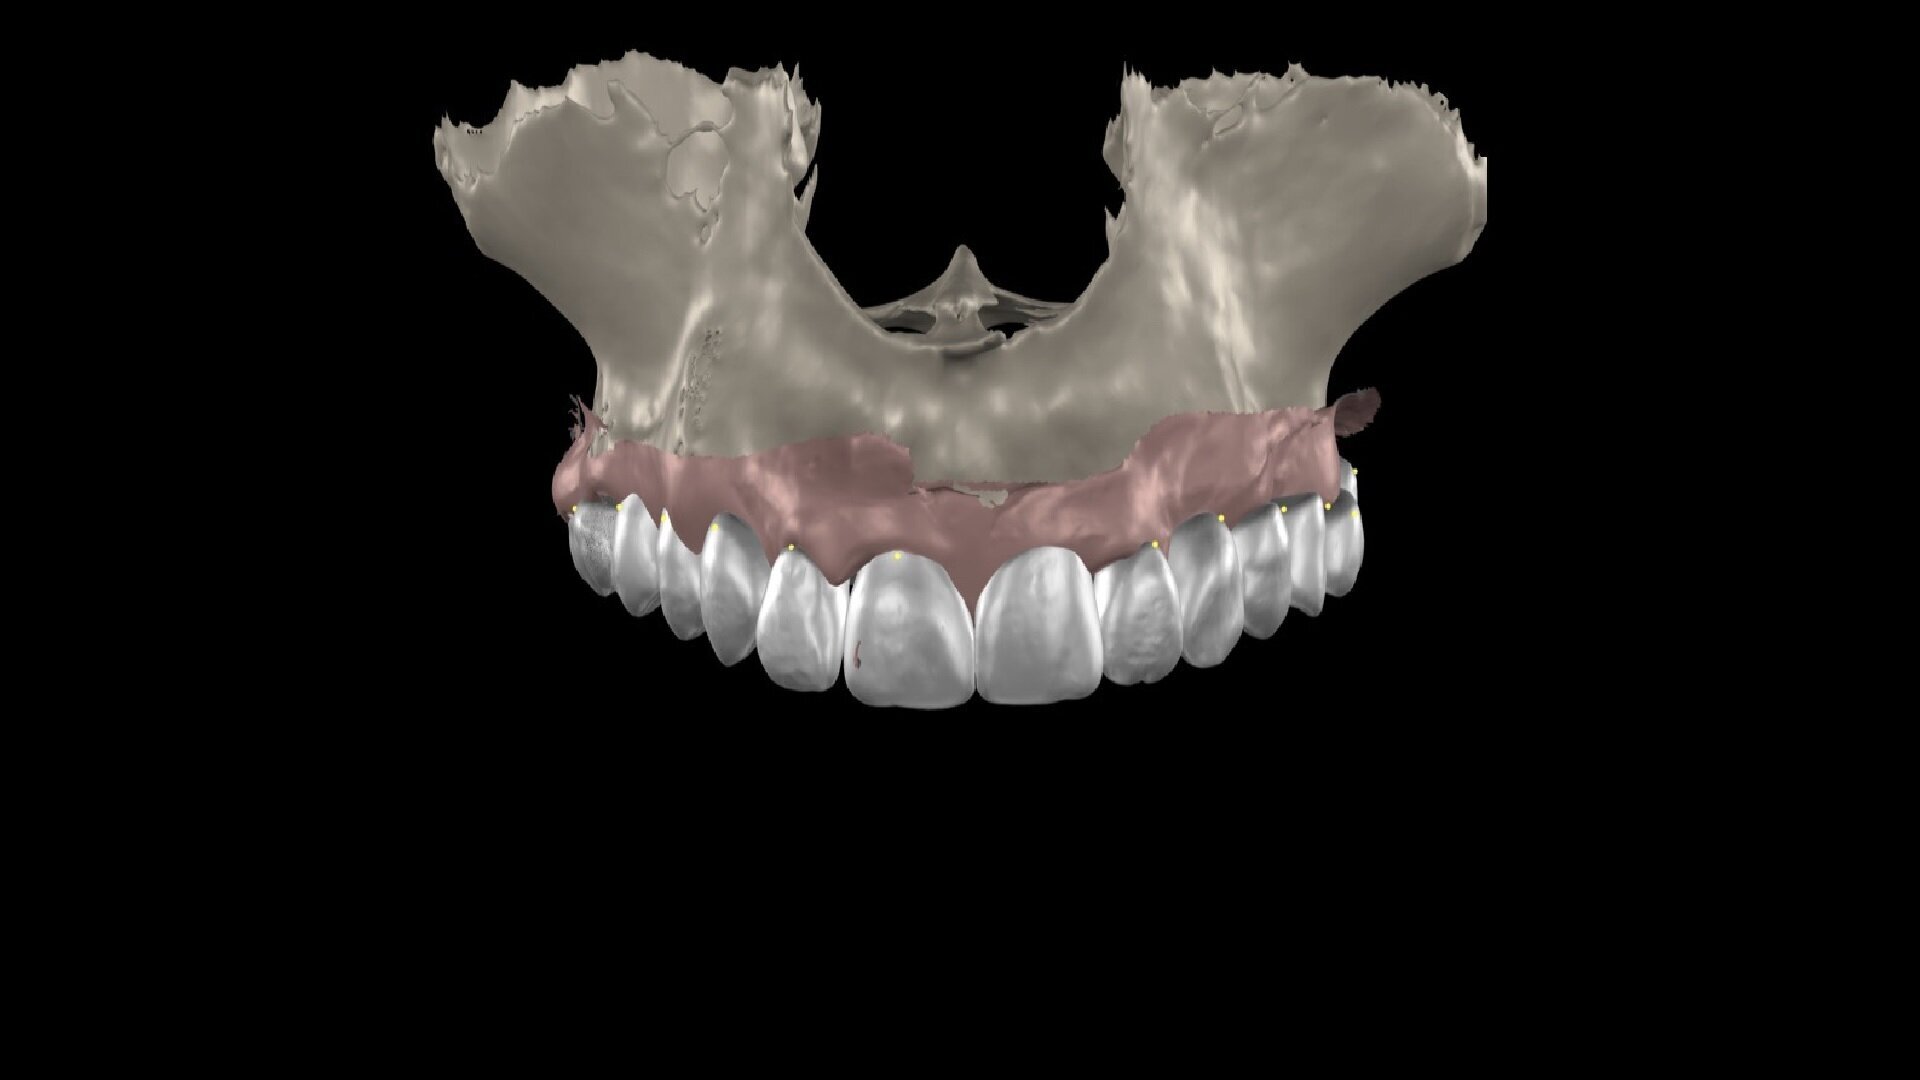

To ensure precise and predictable treatment planning, the DICOM files, STL files and clinical photographs were seamlessly integrated into Smilecloud, utilising advanced artificial intelligence technologies to deliver a highly personalised smile with exceptional precision (Figs. 11–15).

Figs. 11–15: DICOM files, STL files and clinical photographs were integrated into Smilecloud, leveraging artificial intelligence for precise, personalised smile design.